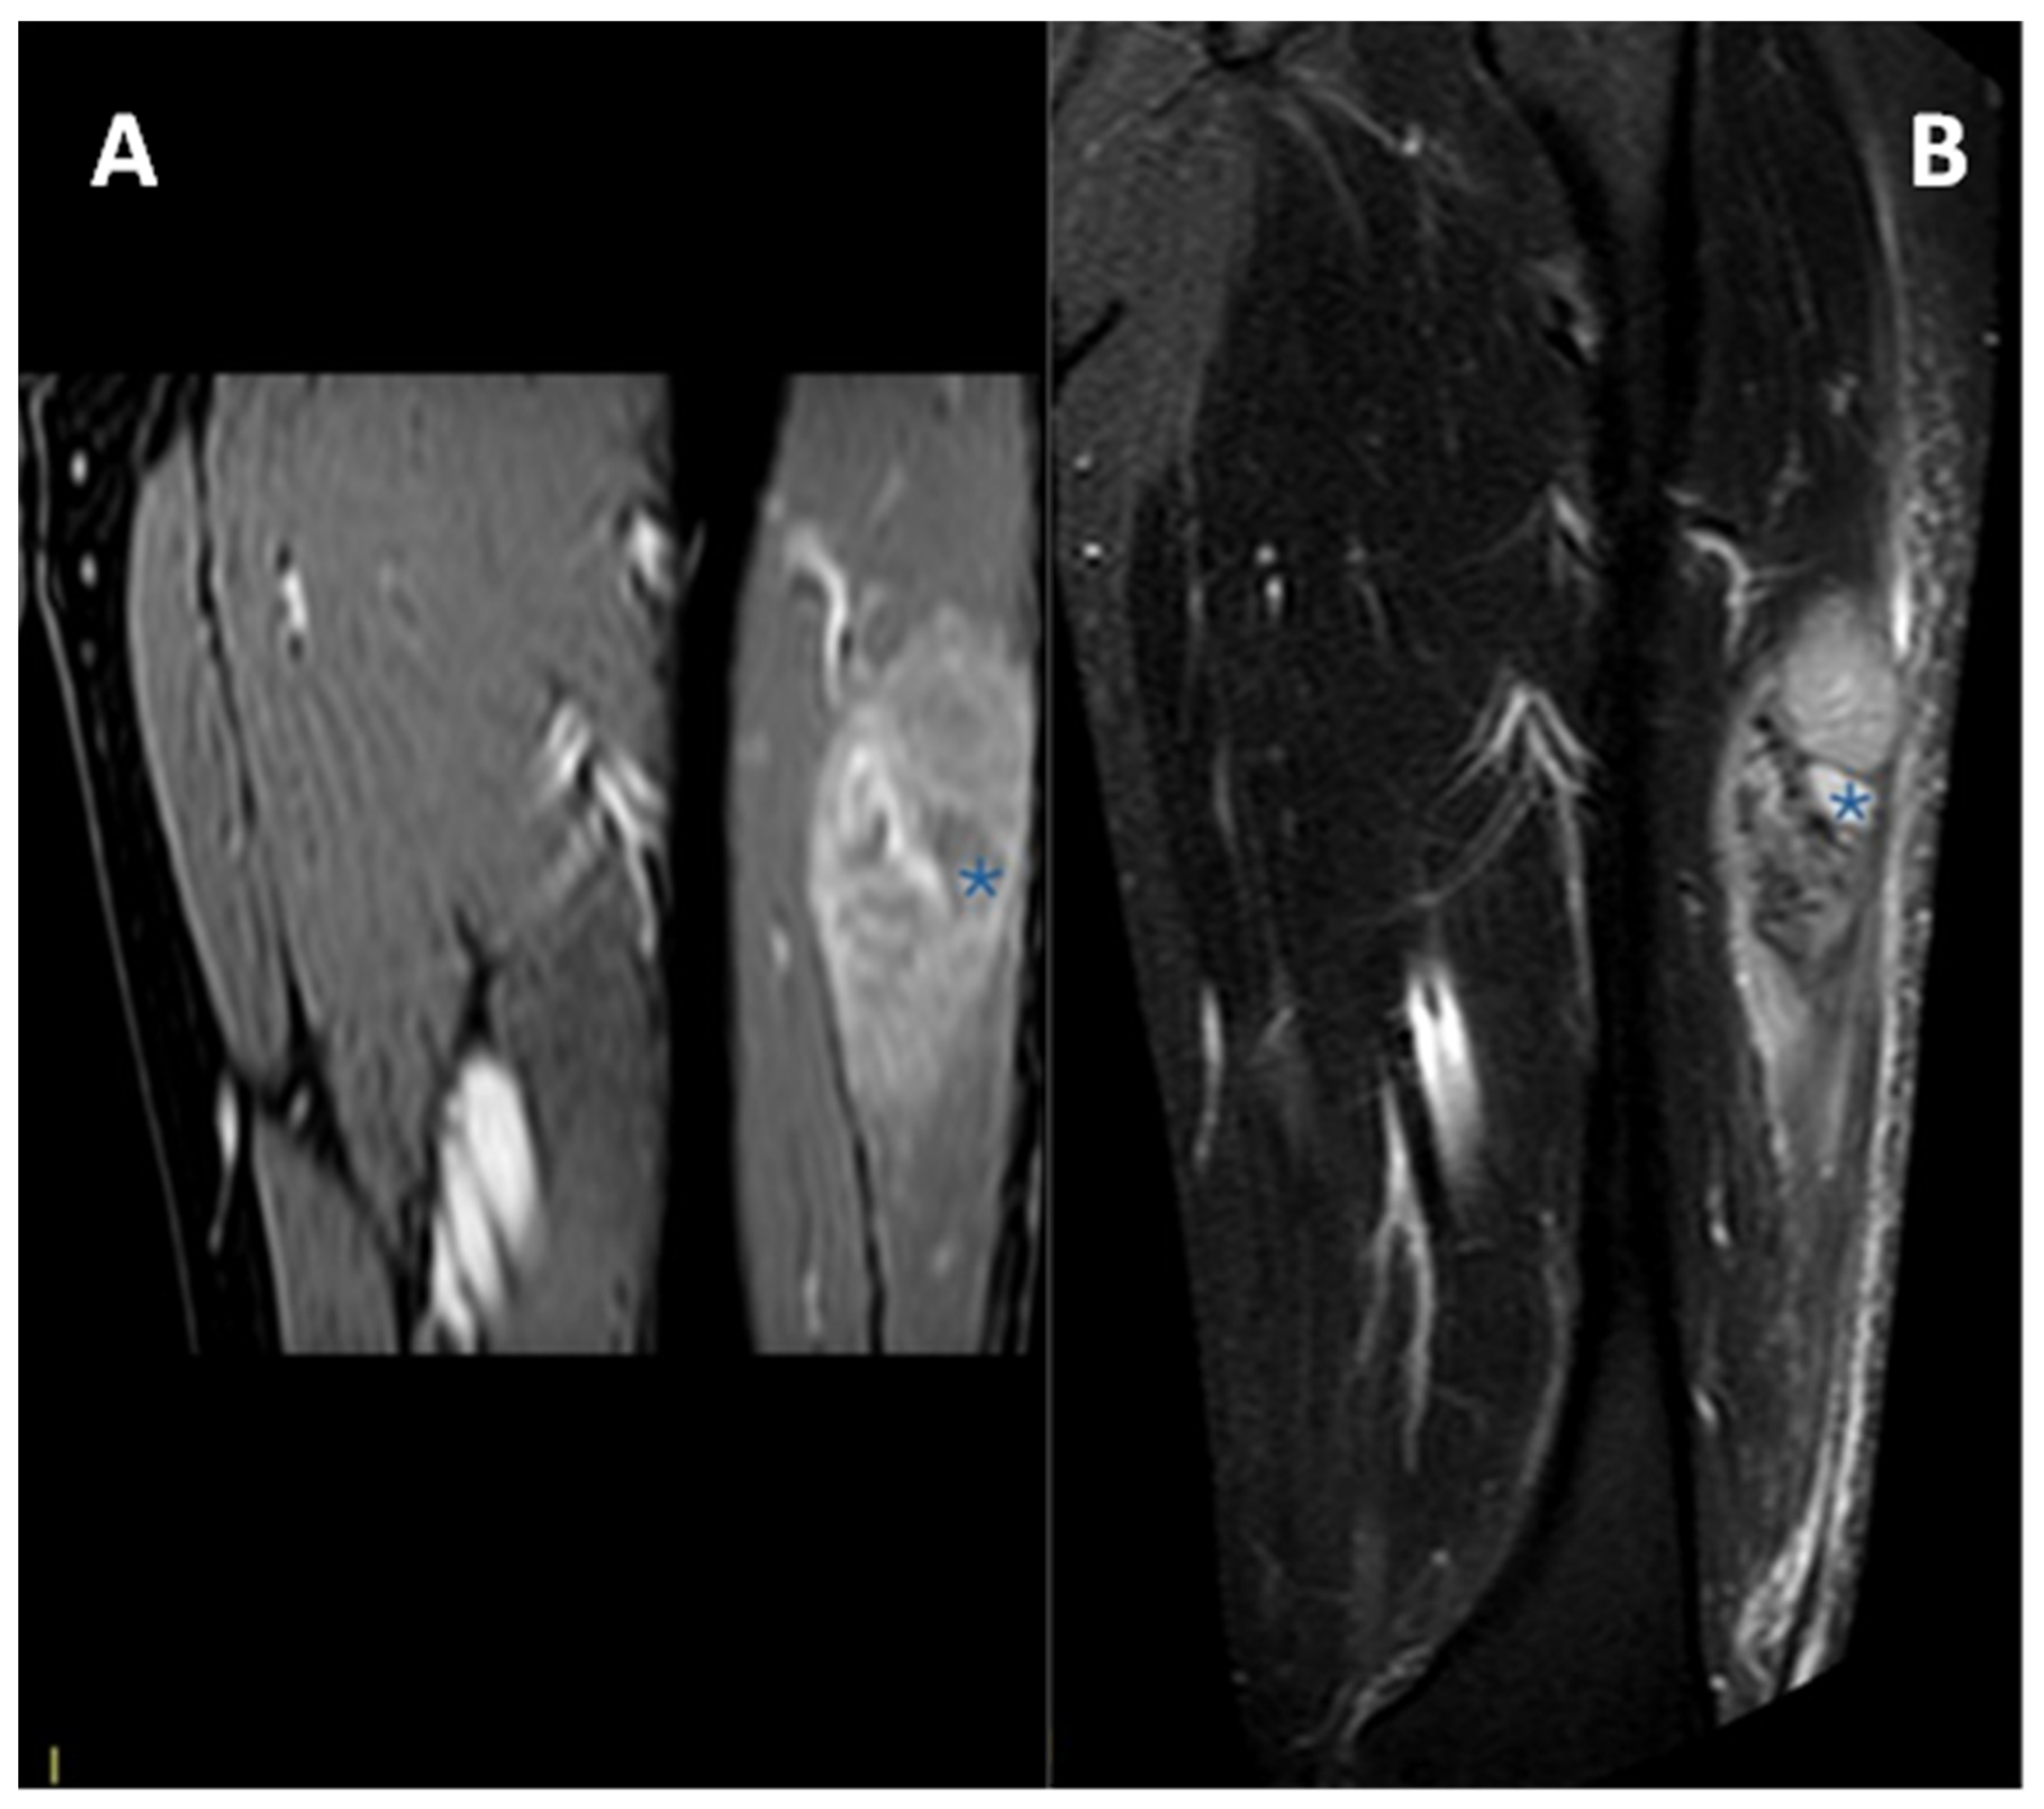

3.4.1. General MRI Features

3.4.2. Peritumoral Edema

3.4.3. Other MRI Features